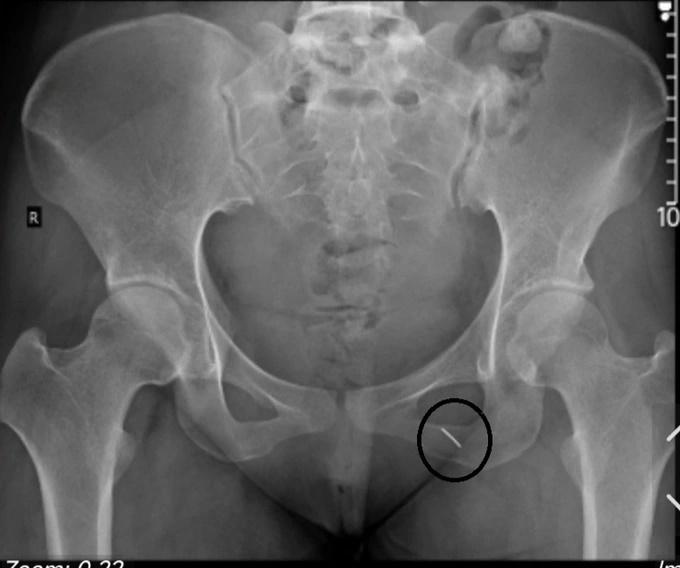

Hình ảnh chụp X-quang cho thấy kim nhọn đâm sâu trong cơ mông bệnh nhân (Ảnh: BS cung cấp).

"Bệnh viện tuyến dưới đã chích da không tìm thấy kim. Trong khi bệnh nhân đang mang thai nên không thể tiếp xúc với tia X, mò dị vật là cây kim nhọn trong cơ thể là không tưởng. Vì thế, sau khi tham vấn các bác sĩ khoa Chẩn đoán hình ảnh (Bệnh viện E), người bệnh được mặc áo chì, chụp đúng phần mông trái để xác định chính xác người bệnh có bị dị vật đâm vào người hay không", BS Hiền thông tin

Khi xác định cây kim nằm sâu trong cơ mông của bệnh nhân, các bác sĩ đã sử dụng hệ thống máy siêu âm 3D, dễ dàng lấy dị vật sắc nhọn bằng kim loại cho người bệnh một cách nhanh chóng. Chỉ sau 5 phút, các bác sĩ đã lấy ra một chiếc kim khâu dài 5cm, chưa hoen rỉ nằm sâu trong cơ mông của người bệnh.